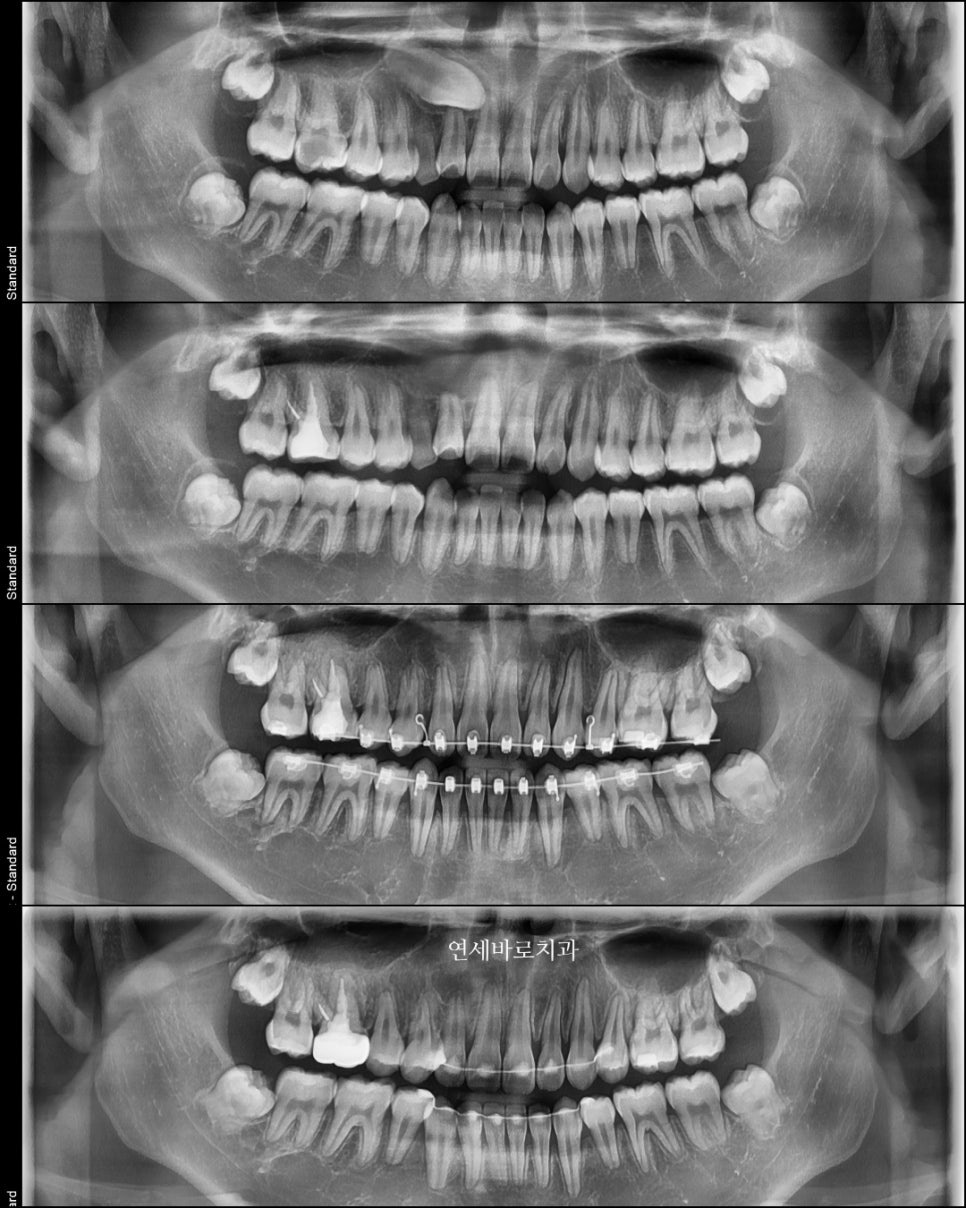

약 1년 반 정도의 치료를 한 아이의 처음과 중간, 그리고 마지막 엑스레이입니다.

매복되어있는 송곳이가 사라졌지만, 끝난 엑스레이를 보면 크게 어색한 것을 모르실 수 있습니다.

이 친구가 매복송곳니를 뺀 이유 중 가장 큰 이유는 노란색으로 표시된 부분의 치아의 뿌리를 녹일 위치였기 때문입니다.

송곳니를 내리면 두번째치아가 손상을 입고

두번째를 빼자니 차라리 송곳니를 빼는게 심미적으로 유리하기 때문에

최종적으로 송곳니를 빼기로 한거죠.